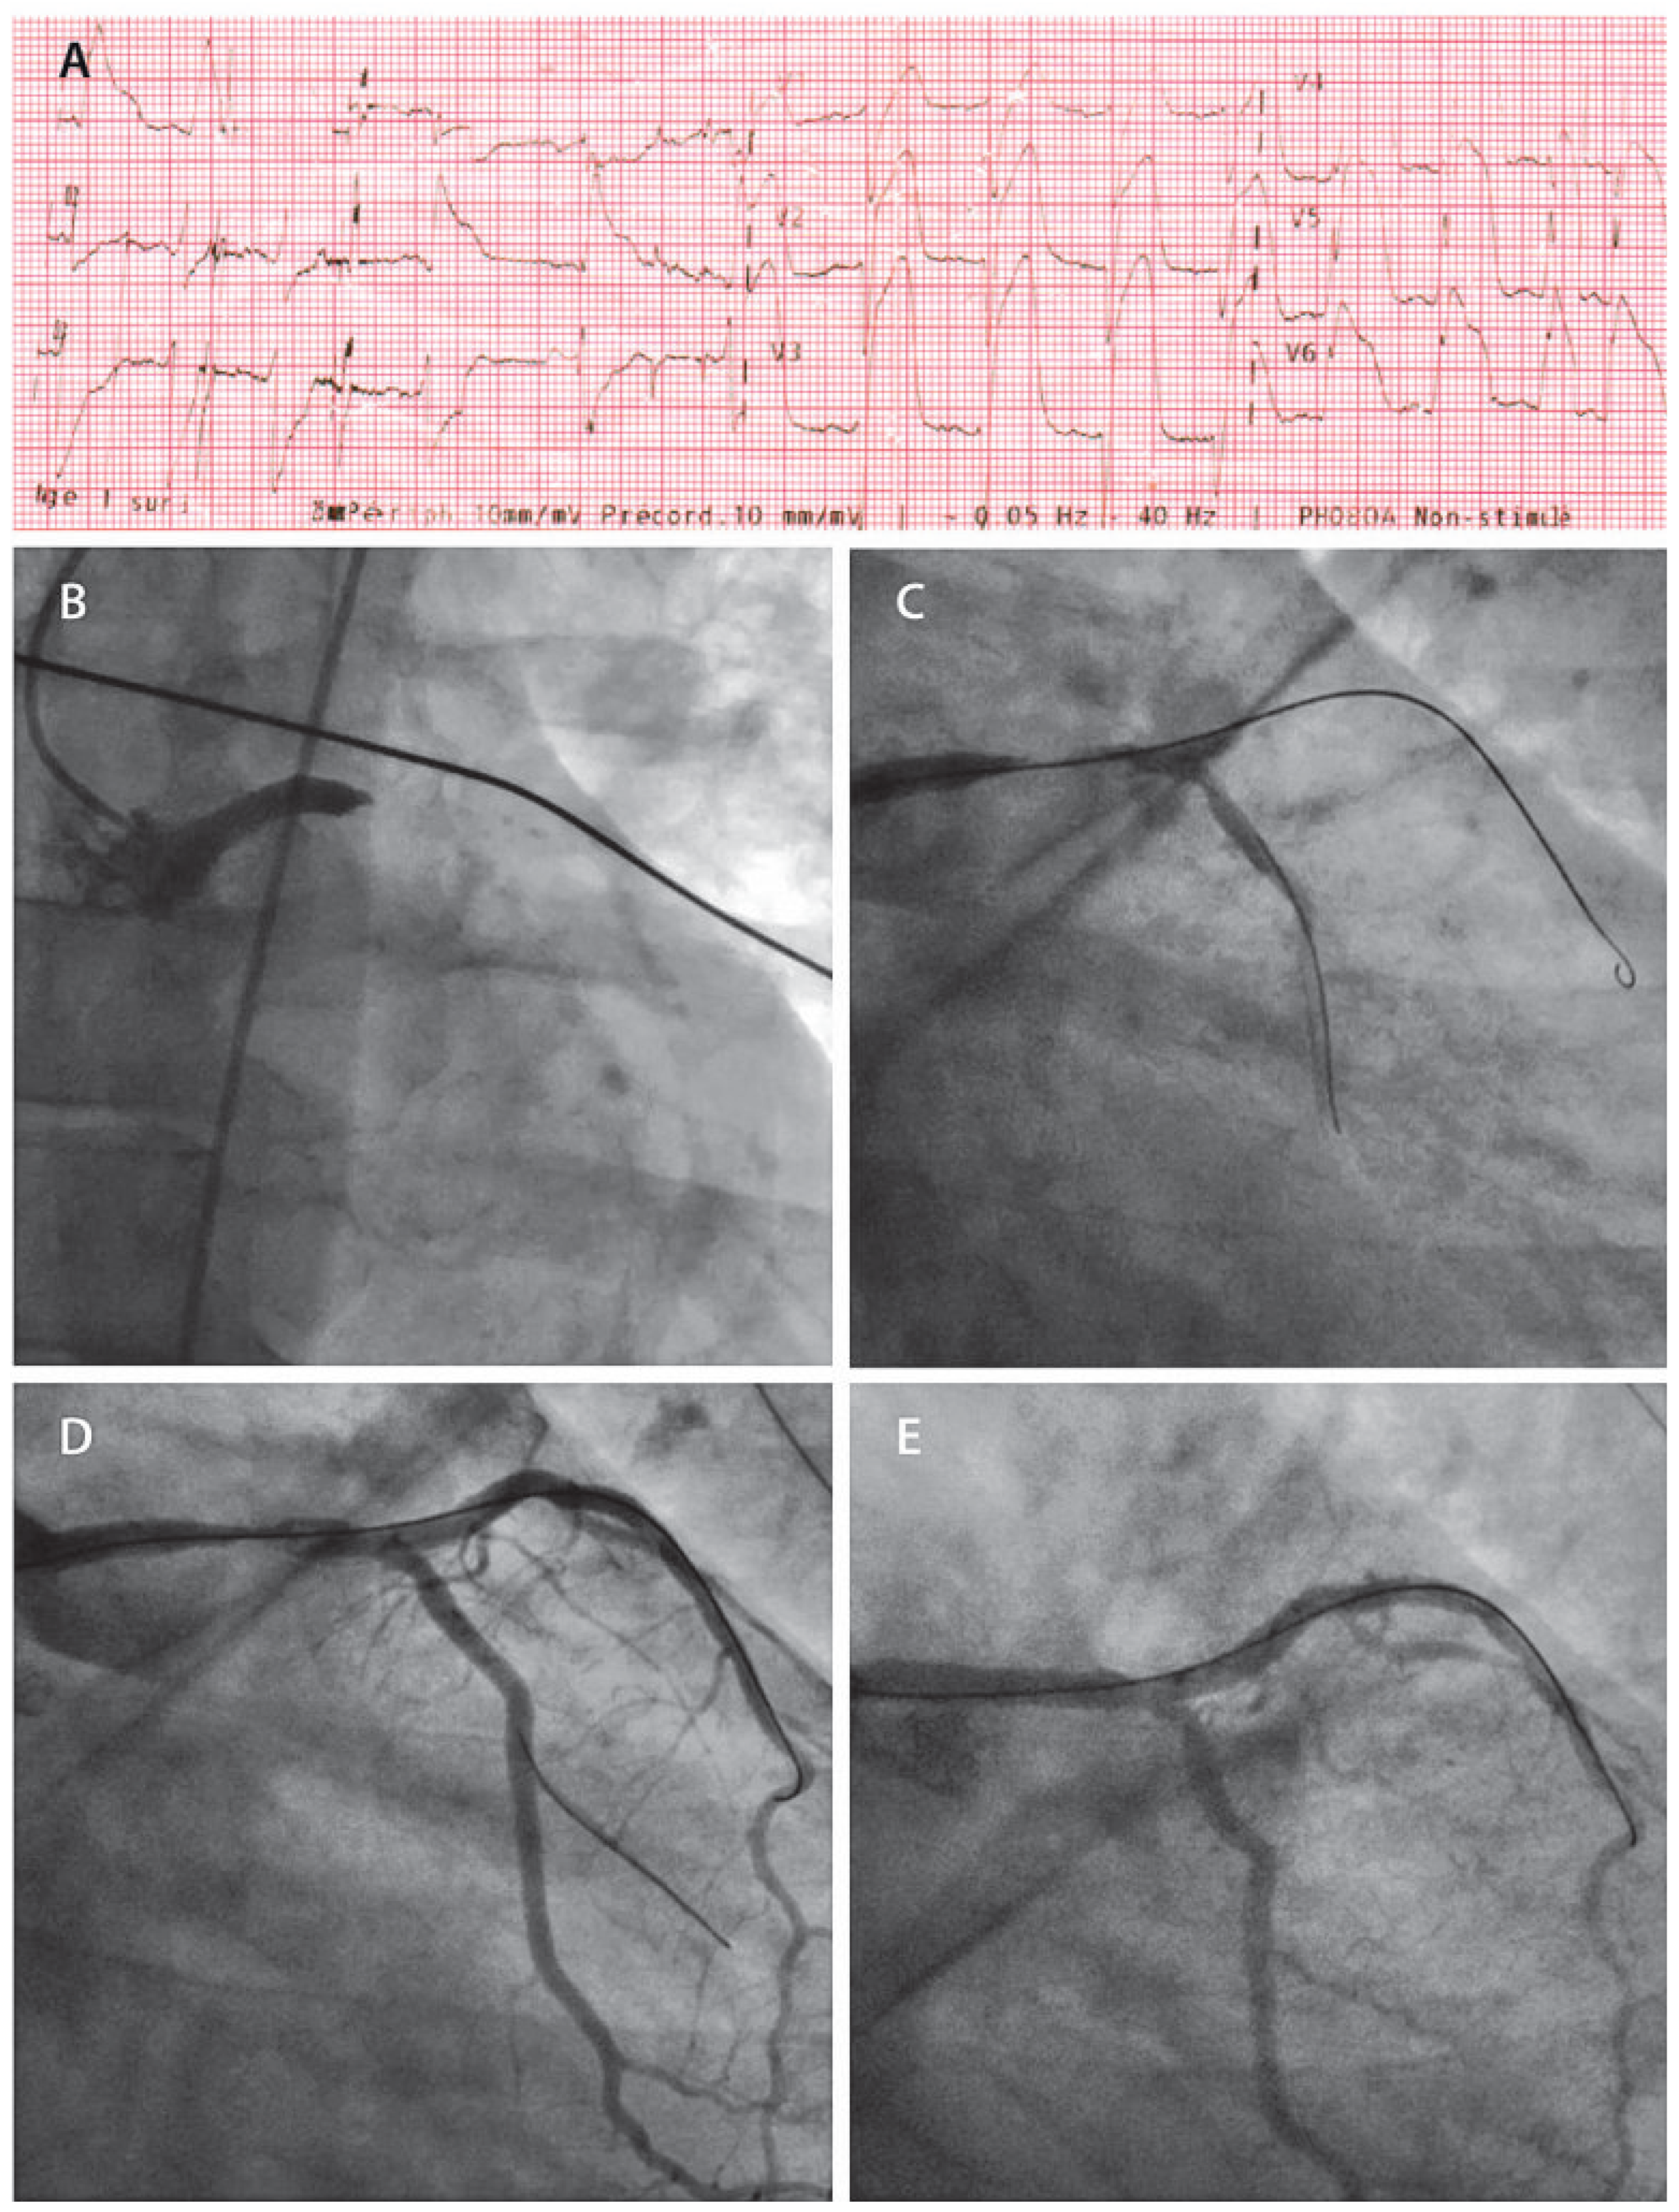

A 37-year-old man, with active smoking and dyslipidemia as cardiovascular risk factors, experienced acute onset chest pain and dyspnea while playing badminton. His game opponent called the paramedics. The physician dispatched with the ambulance performed a 12-lead electrocardiogram showing tombstone ST segment elevation in the anterior leads (Figure 1A), and therefore activated the ST segment elevation myocardial infarction (STEMI) alarm in order to prepare the cardiac catheterisation laboratory at the primary percutaneous coronary intervention (PCI) centre. After administration of 250 mg intravenous (IV) aspirin, 600 mg loading dose of clopidogrel and 5000 IU of IV unfractionated heparin, the patient was brought directly to the cardiac catheterisation laboratory.

Shortly after the beginning of the procedure, the patient developed haemodynamic instability with hypotension and pulmonary oedema. Single injection of the left coronary artery, performed using a right femoral approach, showed a completely occluded left main stem (LMS) in its mid portion (Figure 1B). The diagnostic catheter was then exchanged for a 6 French extra backup 4.0 guiding catheter and two 0.014 wires were advanced into the left anterior descending coronary artery (LAD) and first obtuse marginal (OM). This restored a TIMI II flow (Figure 1C) and allowed appreciation of an isolated mid-LMS plaque rupture not involving the LMS bifurcation. Reperfusion was followed by a sustained ventricular tachycardia which spontaneously cardioverted. Abciximab bolus and perfusion were administered, and thrombo-aspiration was performed with a Diver Catheter (Invatec, Roncadelle, Italy) (Figure 1D) followed by the implantation of a 3.5 × 23 mm drug-eluting stent (Xience Prime, Abbott vascular) and restoration of TIMI III flow (Figure 1E). Stent implantation was limited to the body of the LMS, thus no kissing balloon inflation was performed at the distal bifurcation. The timing intervals between alarm to firstmedical-contact, first-medical-contact to door and door to stent were 9, 29 and 21 min, respectively. Therefore, there was only 50 min between firstmedical-contact to stent implantation and no more than 70 min between symptom onset and revascularisation.

Figure 1. (A) Pre-hospital ECG showing tombstone ST elevation in the pre-cordial derivations and aVR. ST-depression is seen on the inferior leads. (B) First injection in the antero– posterior projection showing an occluded left main stem. (C) Right anterior oblique and caudal projection after advancement of two 0.014 PCI wires. (D) Injection following successful thrombo-aspiration. (E) Result post drug-eluting stent implantation (3.5 × 23 mm Xience Prime) on the body of the left main stem.